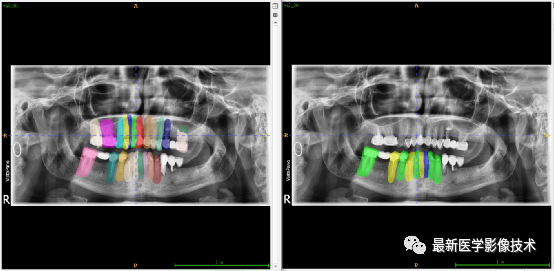

验证集牙齿分割计数和异常牙齿分割识别

左图是分割计数,右图是异常牙齿分割识别结果